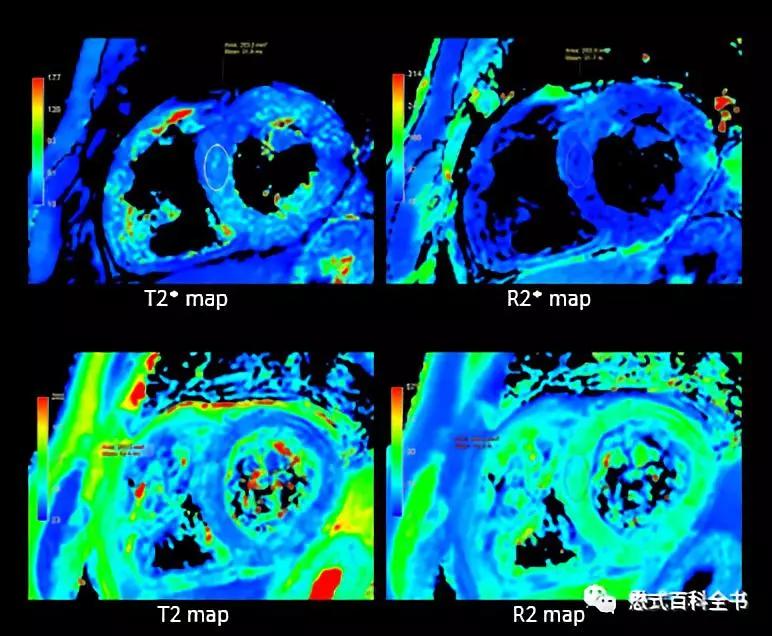

图2:心脏的T2* mapping

和T2 mapping类似,T2* mapping主要是测量组织体素的T2*值。同T2值不同的是,T2*值受其他磁敏感影响比较大,包括铁沉积(铁含量),主磁场均匀性等。

所以在心脏磁共振中,T2* mapping的主要作用当然就是鉴别和定量心肌铁沉积。注:懋式百科全书原创文章并未在搜狐、网易、新浪、趣头条、360个人图书馆、百家号、东方头条发表,也未授权他们转载,如果读者发现很大可能性是机器自动抓取或者人工搬运,也就是说如果这些平台有同样的文章,就是未经授权的非法*取盗**,如果发现请举报。

图10:心肌的T2* mapping和T2 mapping,伪彩图

如果一个组织有铁沉积或者铁过载的话,那么随着回波时间TE的延长,组织信号强度衰减会非常厉害。也就是说铁沉积或者铁含量越多,组织的T2*值越低。

前面说过,心肌组织T2*<20ms,即可以判定为铁沉积。

如果心肌组织15ms≤T2*<20ms,则为轻度铁沉积;

如果心肌组织10ms≤T2*<15ms,则为中度铁沉积;

如果心肌组织T2*<10ms,则为重度铁沉积。